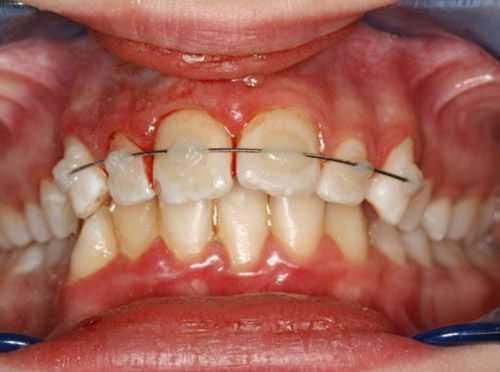

После проведённых лечебных мероприятий вывихнутый зуб иммобилизируют (обездвиживают). Для этого врач использует индивидуальную шину-каппу, изготовленную непосредственно на пациенте. В шину обязательно включают не менее двух здоровых зубов по обе стороны от неполного вывиха. Шину накладывают минимум на 5-6 недель.

Перед шинированием и в динамике лечения проверяют электровозбудимость (реакцию на электрический ток) сосудисто-нервного пучка. Понижение или отсутствие электровозбудимости не только в первые 1-2 недели после травмы не обязательно говорит о необратимых изменениях. Реакция пульпы может приходить в норму в течение нескольких месяцев. Но если обнаруживаются клинические признаки гибели пульпы, её необходимо удалить, а канал пролечить, иначе оставшаяся в канале мёртвая пульпа приводит к развитию острого периодонтита или периостита.

- Если с момента вывиха прошло более 10 часов, пульпу полностью удаляют, а канал после механической и медикаментозной обработки пломбируют. Зуб после реплантации выводят из прикуса и укрепляют путём шинирования с помощью пластмассовой шины-каппы. Снимают её только через 3-4 недели.

Тактика врача при переломе корня определяется характером и локализацией повреждения, возрастом пациента, уровнем смещения фрагментов. При выявлении поперечного перелома апикальной трети с нарушением витальности пульпы проводят экстирпацию коронковой и корневой пульпы, медикаментозную и механическую обработку каналов с последующим их пломбированием временной кальцийсодержащей пастой. После обтурации корневых каналов методом латеральной или вертикальной конденсации гуттаперчи производят хирургическое вмешательство, цель которого при переломе корня зуба заключается в удалении отломанного апикального фрагмента. При сохранении витальности пульпы показана иммобилизация зуба специальной каппой или проволочной шиной, зафиксированной к 2 интактным зубам по обе стороны от поврежденного с помощью жидкого фотополимерного материала.